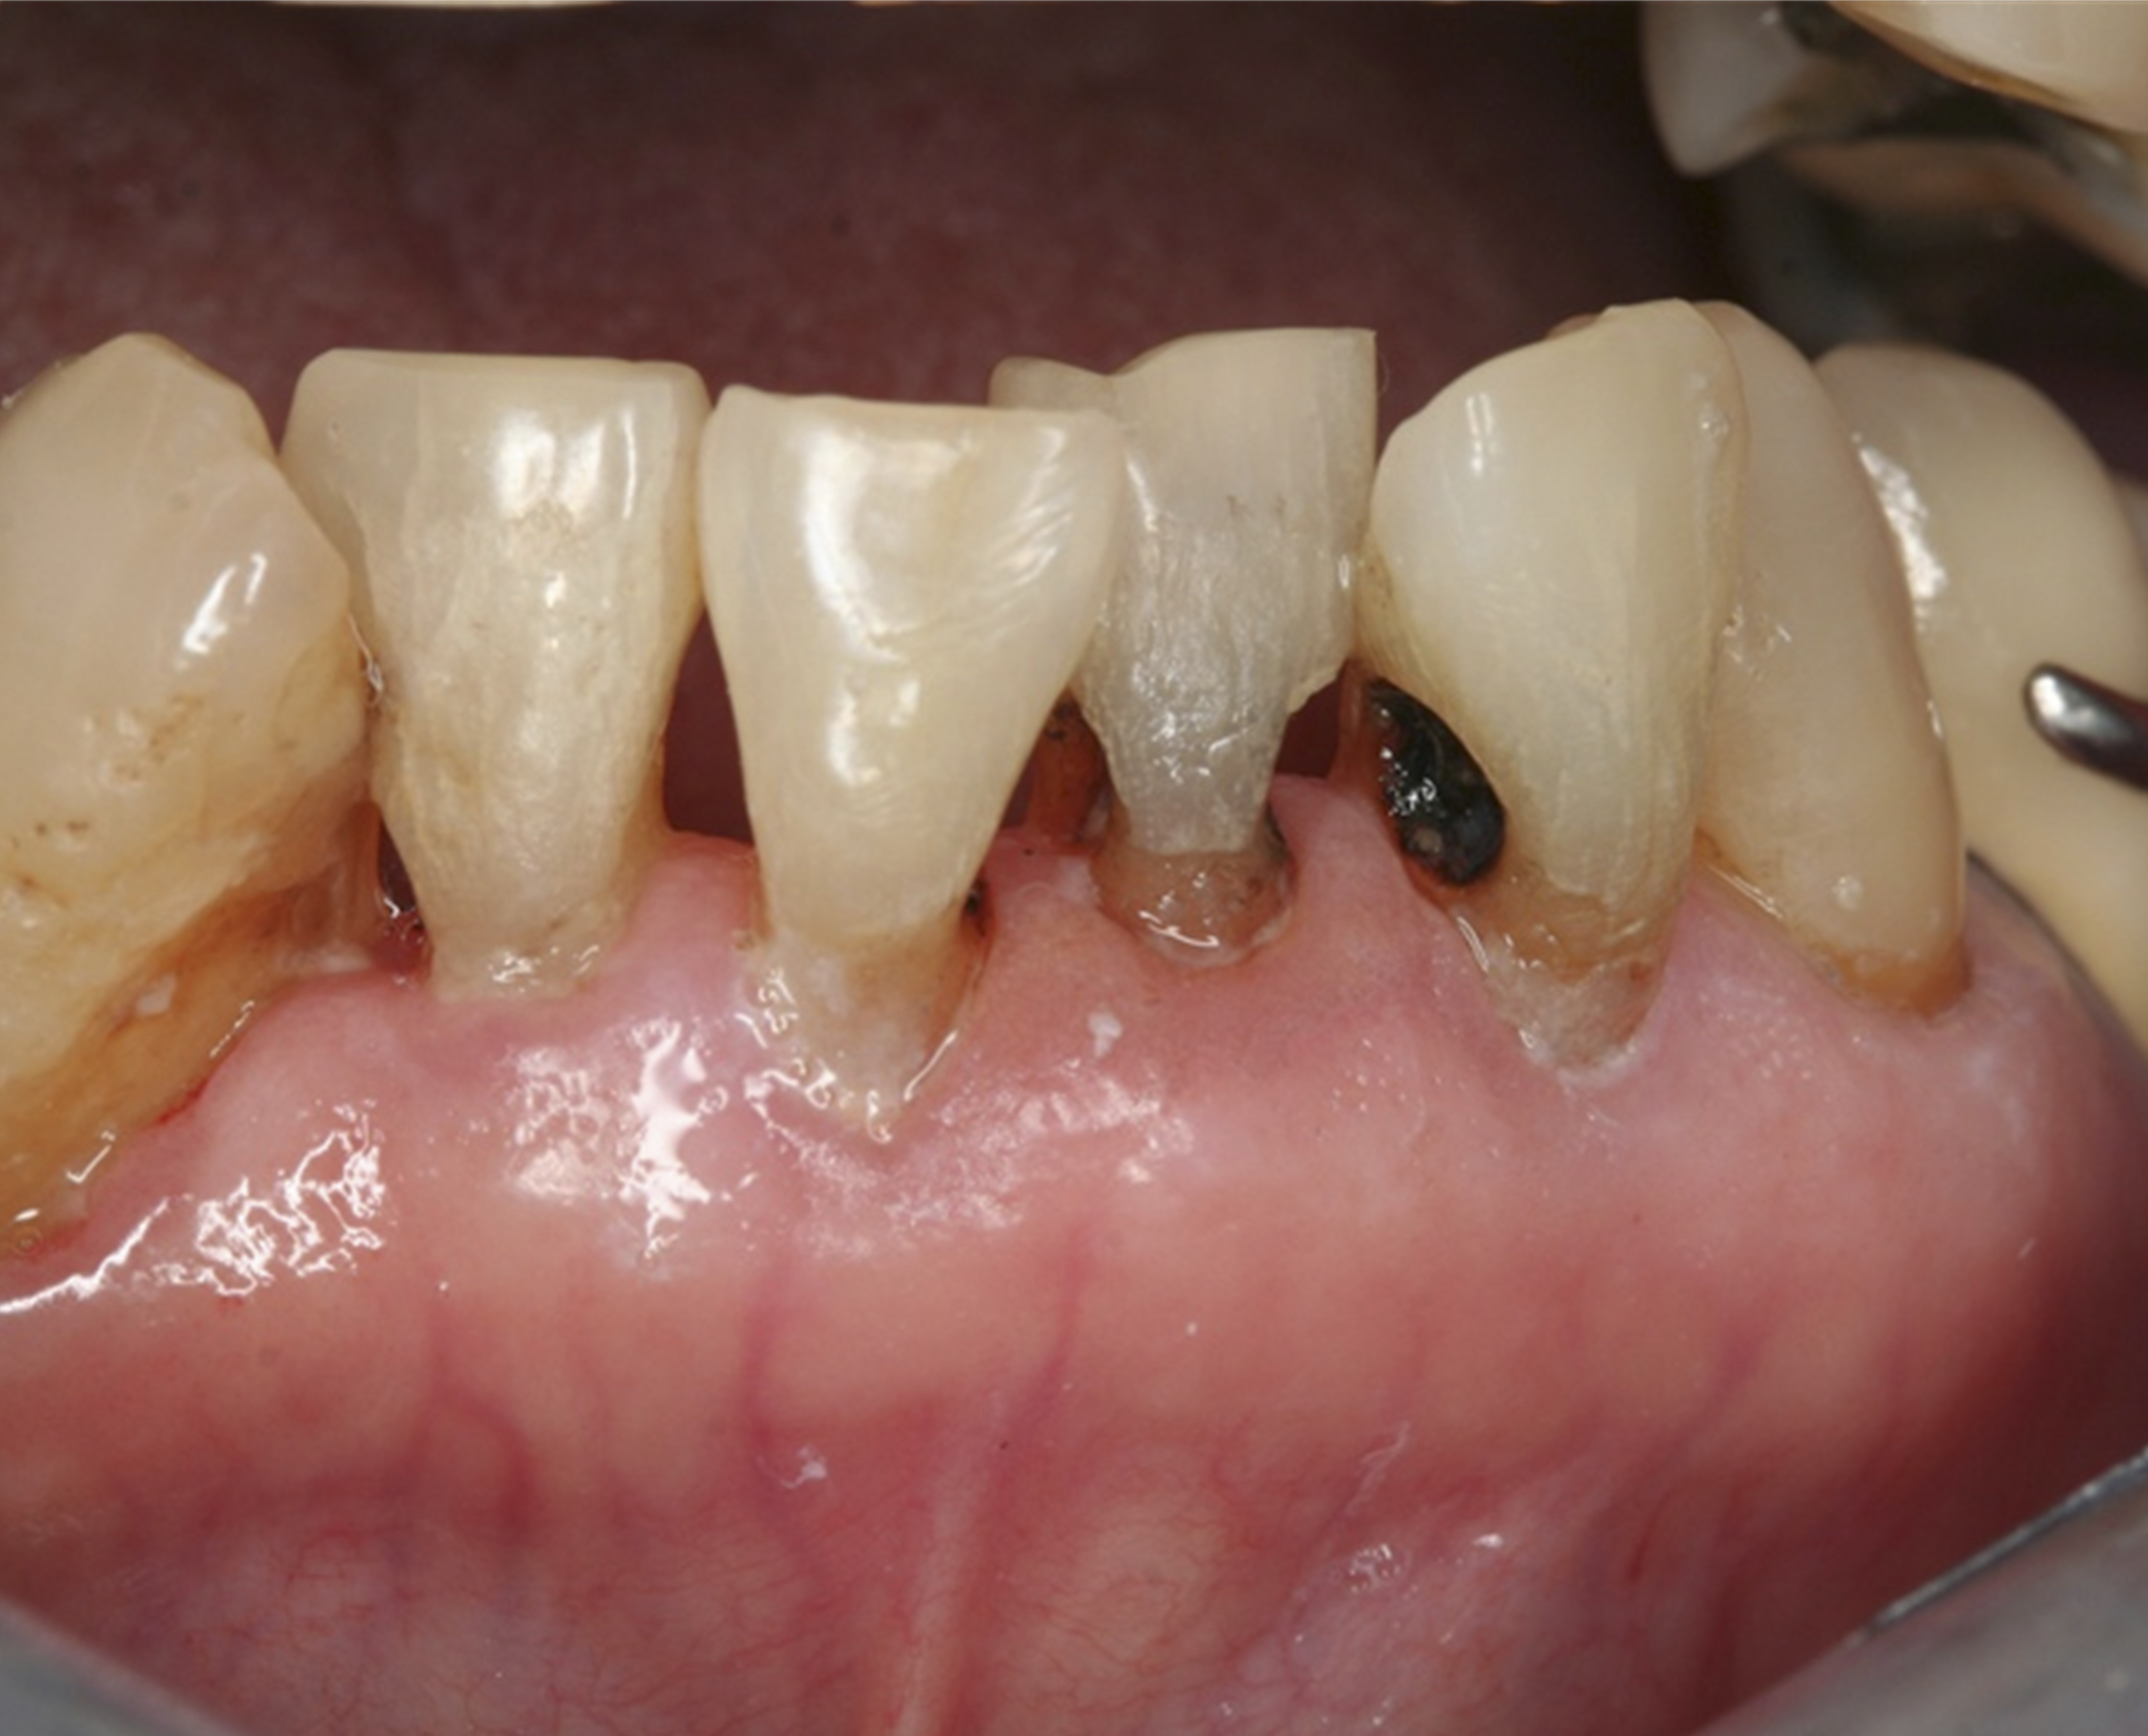

Fig 6. Use of 38% SDF to arrest root caries in permanent teeth of an elderly patient. Fig 6: The arrested root carious lesions were hard to probe.

Figure 6

Fig 7. The lower incisors were responsive to electric pulp testing with no radiographic pathology.

Figure 7